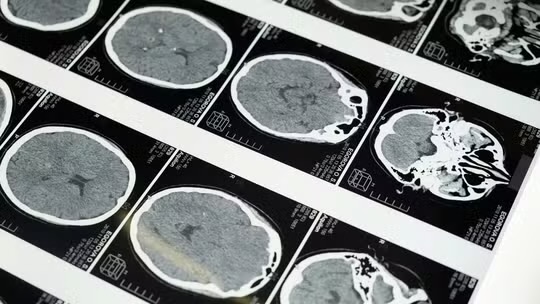

🧠 Ao longo da análise, os pesquisadores acompanharam 4,7 mil pessoas sem Alzheimer ou comprometimento cognitivo e analisaram mais de 12 mil exames de ressonância magnética realizados ao longo de vários anos.

Os participantes tinham entre 17 e 95 anos e passaram por ao menos dois exames, com intervalo médio de três anos.